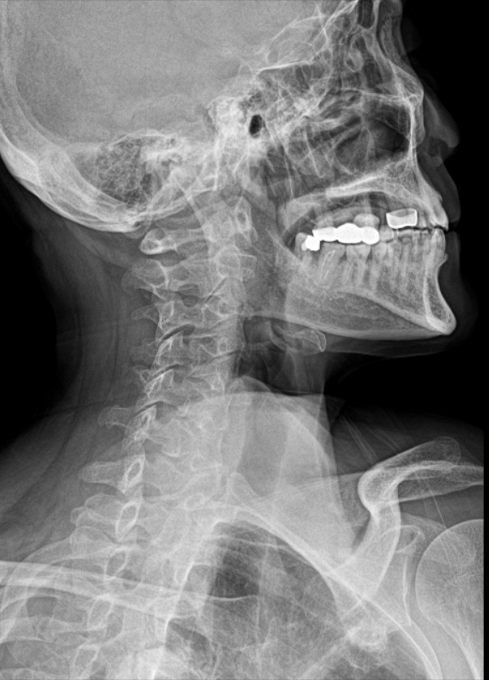

头颈正位片

灰阶对比突出,细节丰富